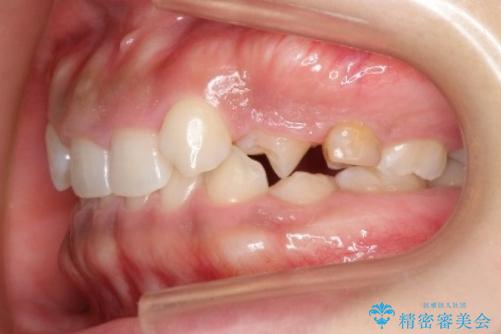

- 後続永久歯が欠損した患者様です。

矯正治療にて歯並びを改善したのち、インプラントにて咬合回復を行う治療計画としました。

捻転が強い部分だけはワイヤーの部分矯正で対応しております。